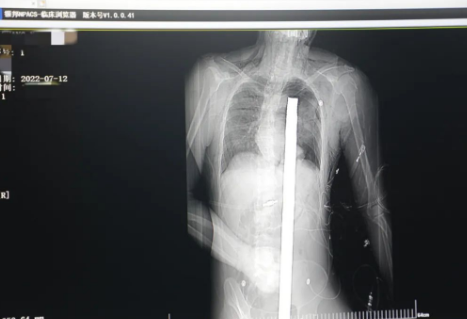

突發(fā)!太疼了,1.2米長的螺紋鋼從男子會陰部垂直穿入胸腔......7月12日下午16時10分,西安一處工地的一名26歲工友,不慎從10多米的高空墜落,不幸的是工地上一根直徑3厘米的螺紋鋼從男子會陰部垂直穿入體內,工地上的工友們小心翼翼地將連著的鋼筋截斷。情況危急,立即送往西安國際醫(yī)學中心醫(yī)院急救中心,此時正是下午17時00分。

時間就是生命!此時,西安國際醫(yī)學中心醫(yī)院展開了一場與生命賽跑的搶救,第一時間開辟綠色通道,急診X光片及CT顯示:異物經會陰部貫穿盆腔、腹腔到達左側胸腔主動脈弓水平。醫(yī)院創(chuàng)傷中心立即啟動應急預案,劉延彤副院長親臨指揮,下午17點48分,當患者被送達手術室,胸外、心外、肝膽外科、胃腸外科,泌尿外科及麻醉科等多學科專家聯手對這名工友進行“縱劈胸骨 前外側開胸探查 氣管及主支氣管修補 肺修補 血胸清除 開腹探查止血 腹膜后及盆腔探查......”手術。

情況緊急!術中探查后發(fā)現,長120cm直徑3cm的螺紋鋼經患者右側會陰部穿入,傷及直腸,途徑膀胱后方,左側髂總動靜脈之間傷及左腎后,經胰腺后方在肝脾之間穿破膈肌,在下肺靜脈前方穿入左肺穿破氣管及左右主支氣管膜部,止于主動脈弓下水平,穿入體內的部分達到75cm。